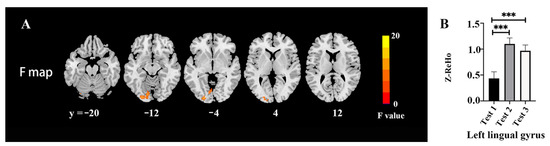

3.5. VMHC Values

| Area | Broadmann Area | Volume (Voxels) | Talairach | F (Peak) | ||

|---|---|---|---|---|---|---|

| X | Y | Z | ||||

| Occipital/Lingual_L/Fusiform_L/Calcarine_L | 17/18/19 | 179 | −24 | −93 | 6 | 19.93 |